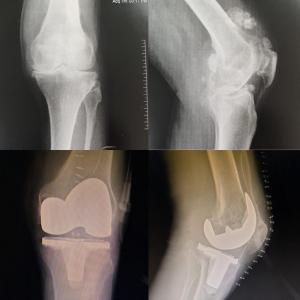

Revision Knee & Hip Replacement

Complex Joint Replacement Surgery